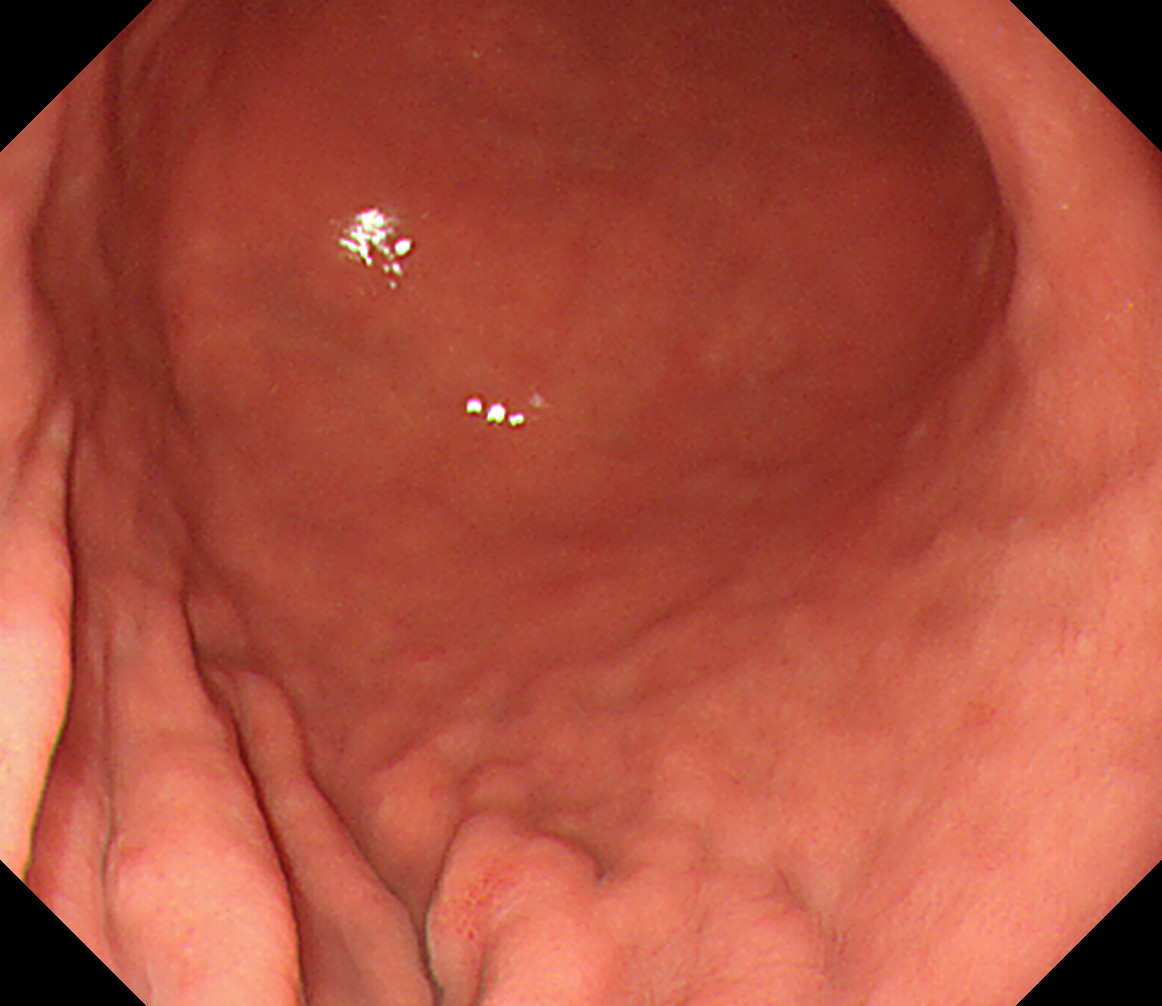

23 胃角部大弯 以下ずっと[見下ろし]でくるくる反時計方向に回しながら引き上げていく

萎縮境界の観察なども行います

胃角部大弯

24 体下部後壁 引き上げて

後壁から反時計回り

接線になり見逃しやすい部位です

体下部後壁

25 体下部小弯 体下部小弯

26 体下部前壁 体下部前壁

27 体下部大弯 噴門部小弯[J反転]